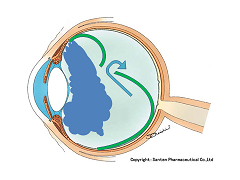

黒目(角膜)から入ってきた光は、目の奥の方のフィルム(網膜)に当たります。網膜は一つの束(視神経)になって、最終的には脳ミソにつながり、「物が見える」という事になります。

図の赤矢印の部分は視神経乳頭と言って、網膜が集まって束になる部分なのですが、実はこの部位のみ光を感じ取ることはできないのです。

写真だと水色の部分が視神経乳頭(マ盲点)になります。ちなみに、物を見る中心部の網膜は黄斑と呼ばれ、オレンジの矢印に当たります。